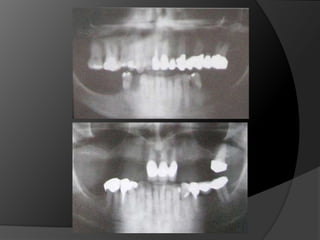

Diagnóstico y Planificación MultidisciplinariaHistoria ClínicaAnamnesisFotografía clínica Montaje modelos de estudioEncerados DiagnósticosEvaluación Radiográfica Radiografías PeriapicalesRadiografía PanorámicaEvaluación DentalEvaluación PeriodontalEvaluación EndodónticaEvaluación OclusalEvaluación Articular?

Diagnóstico y PlanificaciónMultidisciplinariaHistoria ClínicaAnamnesisFotografía clínica Montaje modelos de estudioEncerados DiagnósticosEvaluación Radiográfica Radiografías PeriapicalesRadiografía PanorámicaEvaluación DentalEvaluación PeriodontalEvaluación EndodónticaEvaluación OclusalEvaluación Articular?